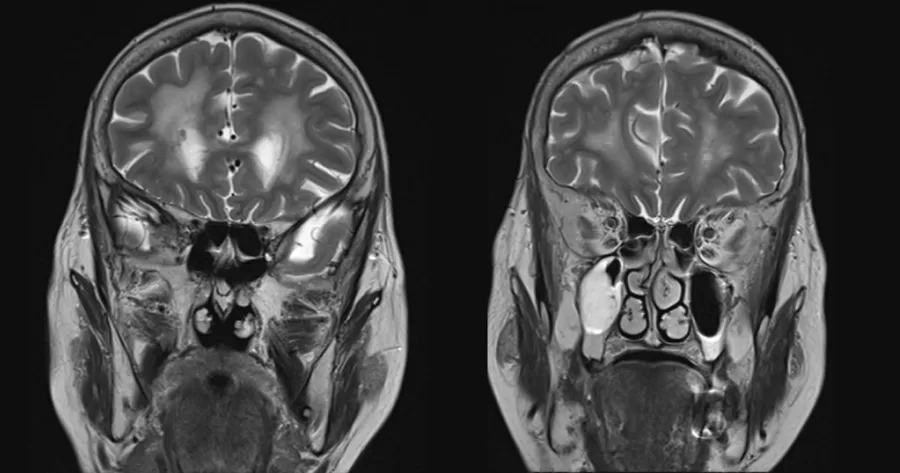

Son araştırmalar, Alzheimer hastalığıyla ilgili dikkat çekici bir bulgu ortaya koydu. Bazı hastaların, ölen donörlerden alınan insan büyüme hormonuyla tedavi edildikten sonra Alzheimer belirtileri gösterdiği tespit edildi. Bu çalışma Alzheimer hastalığının hipofiz bezlerinden alınan örneklerle ilişkilendirilen insan büyüme hormonunun kontamine olmasıyla bağlantılı olabileceğini ortaya koydu. Araştırmacılar, bu hormonların kullanılan örneklerin beyinlerinde hastalığı tetikleyen proteinlerle kirlenmiş olabileceğini düşünüyor. Uzmanlar, Alzheimer'ın günlük faaliyetler veya rutin bakım yoluyla bulaşabileceğine dair herhangi bir kanıt olmadığını vurgularken, bu durumun yalnızca insan dokusu veya kontamine hipofiz hormonu ile aşılanma gibi nadir durumlarda ortaya çıkabileceğini belirtiyor.

Alzheimer'a benzer prion hastalıklarıyla ilgili yapılan yeni araştırmalar, beyinde yayılan bulaşıcı proteinlerin rol oynadığı benzerlikler ortaya koydu. İngiltere'de 1959 ve 1985 yılları arasında kullanılan insan büyüme hormonlarının, bazı hastalarda Alzheimer benzeri semptomlara neden olabileceği belirtiliyor. Kontamine hormon örneklerinin kullanılmasının ardından bazı hastaların Alzheimer'a yakalandığı ortaya çıktı. Araştırmacılar, Alzheimer'ın hipofiz hormonlarıyla ilişkisinin, hastalığın farklı bir kökene veya amiloid-beta'nın farklı türlerine bağlı olabileceğini öne sürüyor.